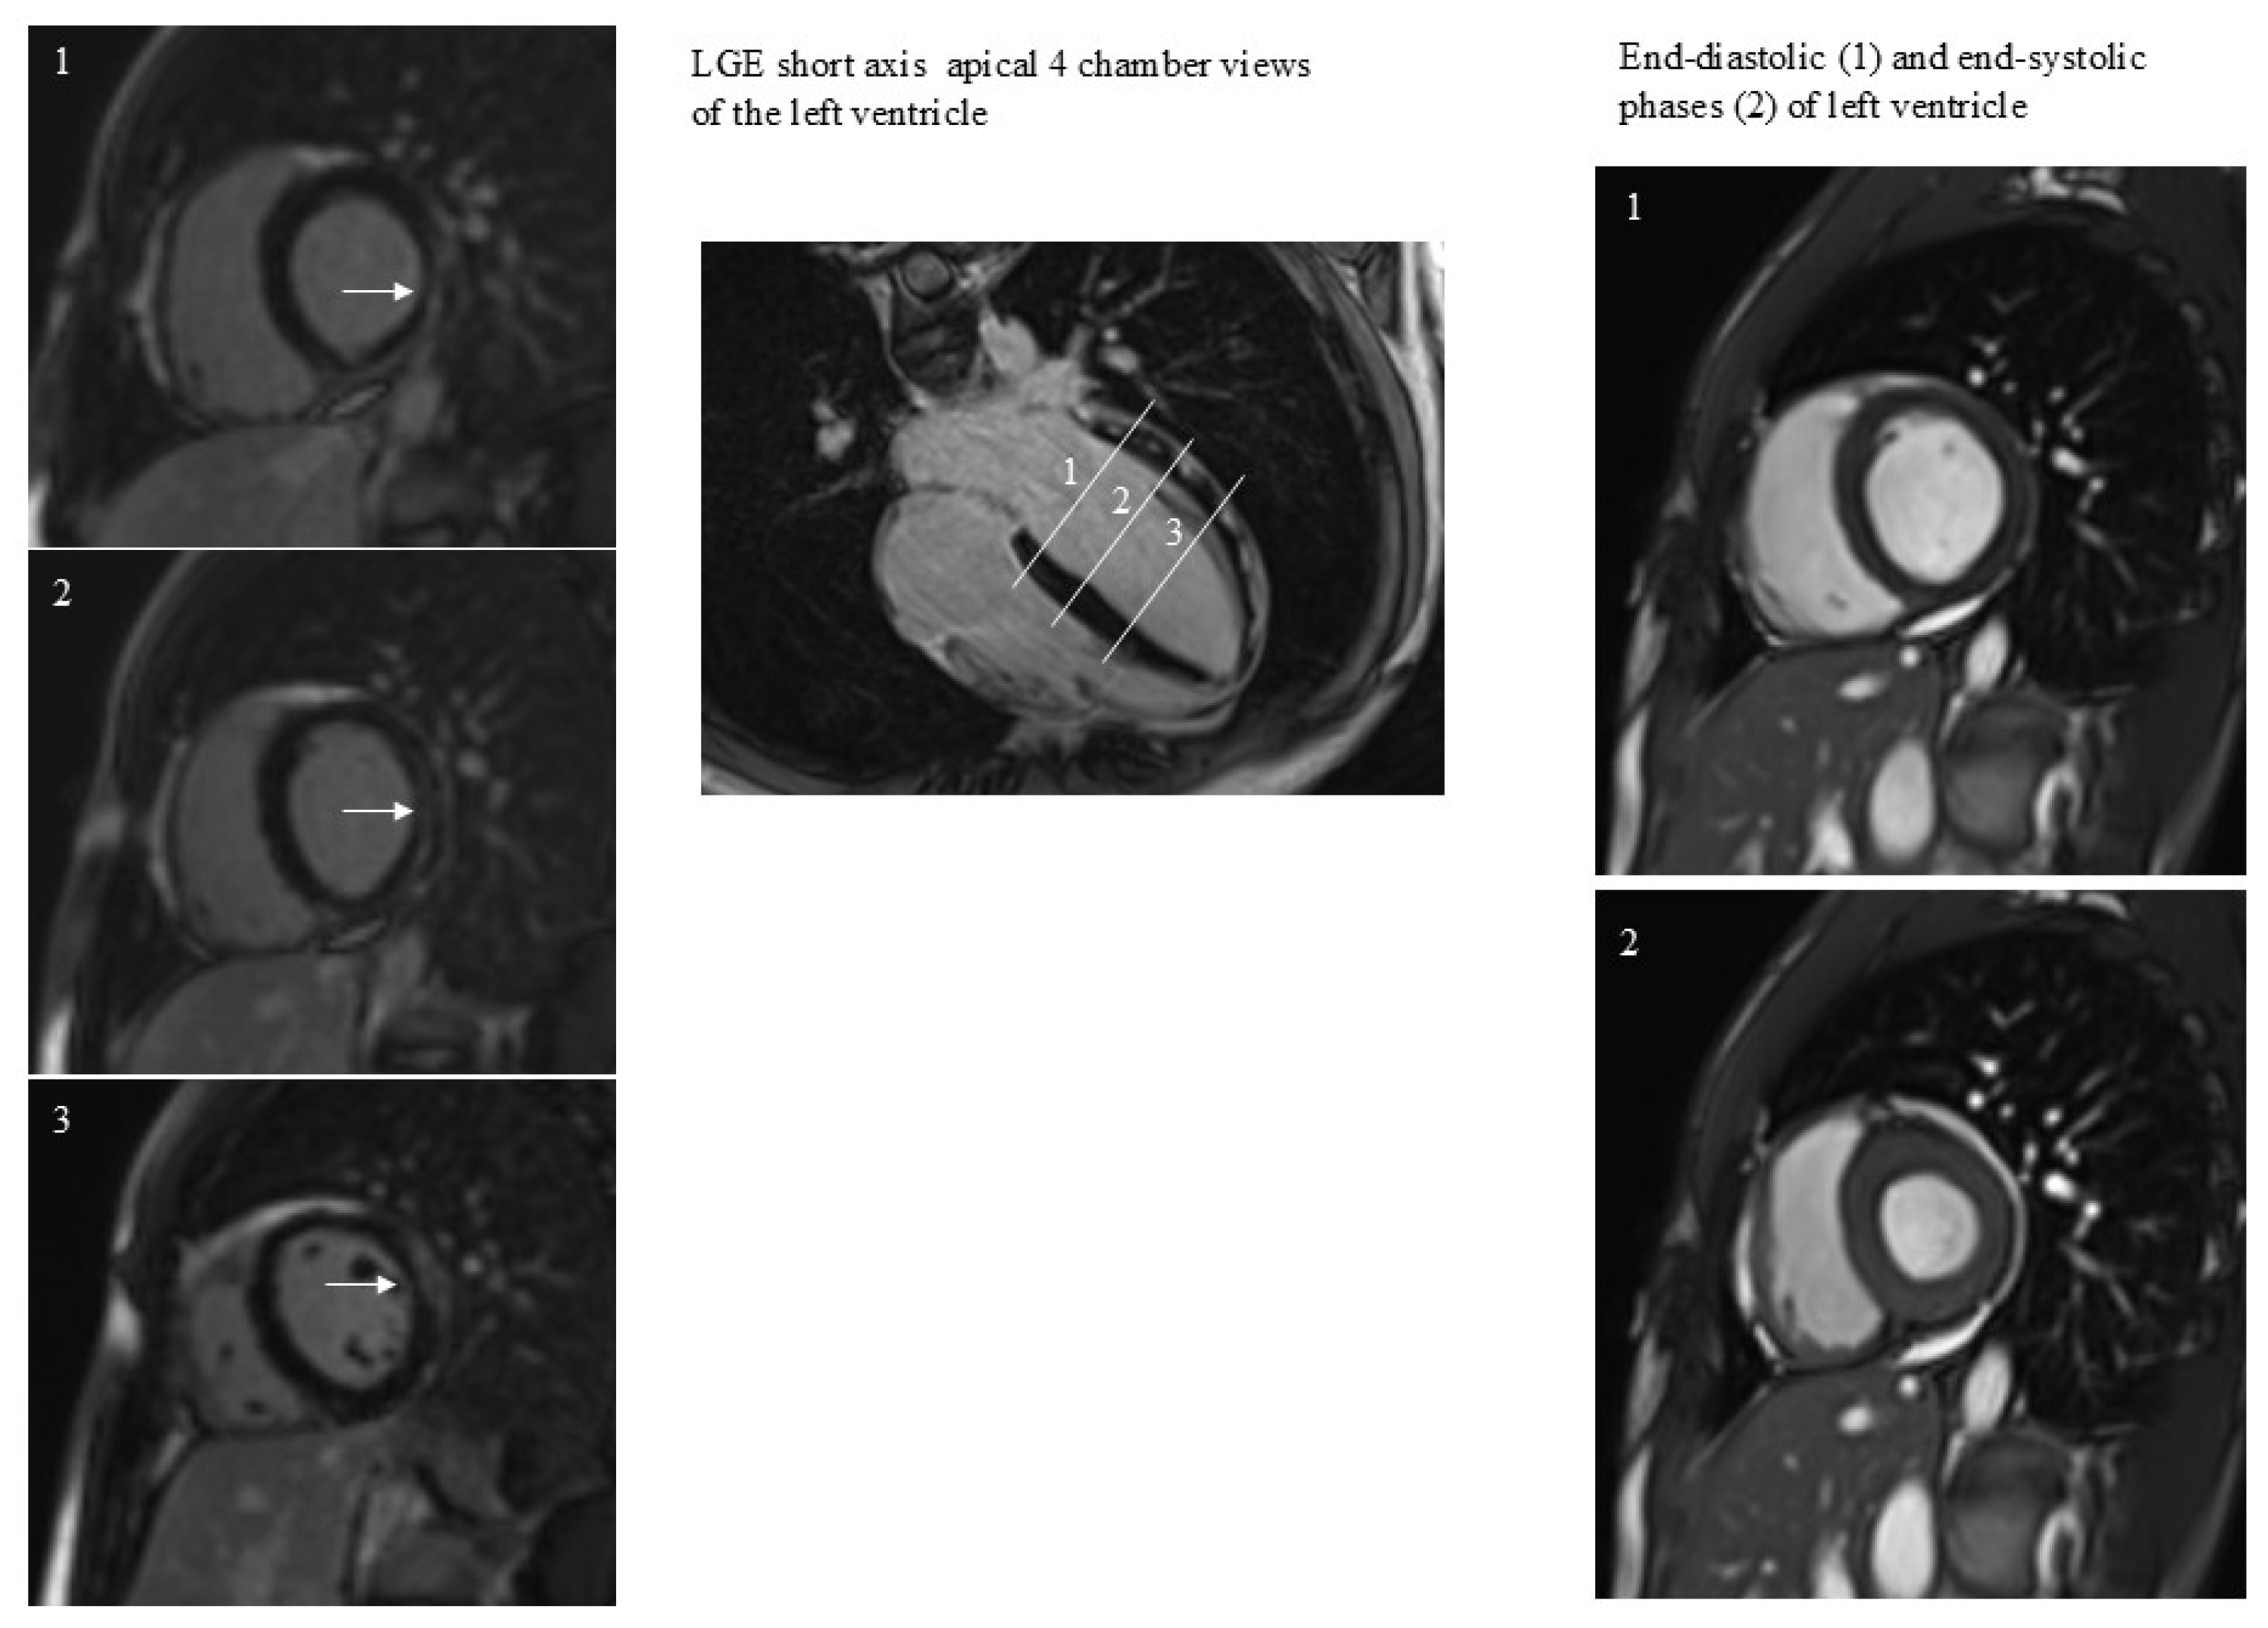

All patients performed CMR examination without any kind of complication. The time interval between COVID-19 diagnosis and CMR was 409 ± 26 days. The prevalence of positive LGE was 33% (17/51). LGE was present in the lateral wall in all patients except for one patient, with LGE positivity at the level of the interventricular septum (Figure 1). In this patient LGE was associated with abnormal regional wall motion (hypokinesia). In general, patients, both with and without positive LGE, had similar CMR variable values (Table 1). The factor associated with LGE was the duration of hospitalization (Figure 2).

Figure 1.

A case of subepicardial and intramyocardial LGE (arrows). LGE persistence was not associated with dilatation or regional dysfunction of the left ventricle. The 3 white lines correspond to the 3 short axes planes on the left.